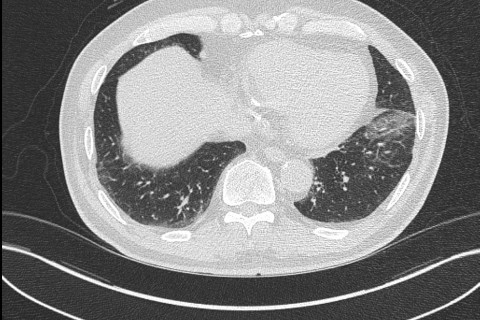

숨케어한의원에서는 전화예약을 받고 있습니다. 내원시 엑스레이, CT사진, 폐기능검사지를 가지고 오시면 자세한 상담이 가능합니다.